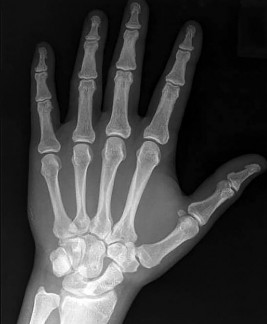

A 12-year-old obese boy presents with left hip pain and an obligate external rotation of the hip during flexion. A radiograph is shown below. What is the most appropriate initial management for the condition demonstrated?

Explanation

The clinical presentation and radiograph represent a stable Slipped Capital Femoral Epiphysis (SCFE). The gold standard for initial management of a stable SCFE is in-situ pinning, typically utilizing a single partially threaded cannulated screw placed in the center-center position of the epiphysis to prevent further slip and promote physeal closure.